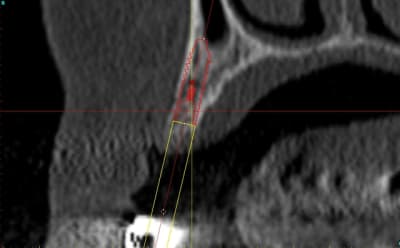

2:

Ostéotome "lame" angulé

lame 15 (fréquent dans ce cas )

Ostéotome droit

tous sont manipulés avec douceur, mais aussi impactés avec le maillet chirurgical